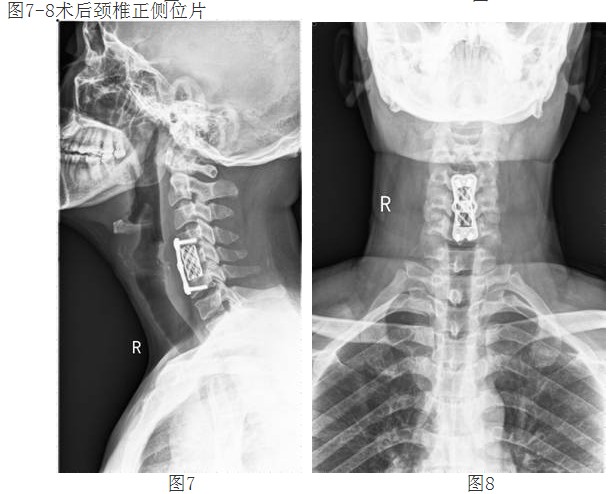

经过谭主任和全科医护人员充分的术前准备和讨论,对患者实施了颈椎前路颈4/5、颈5/6椎间盘摘除、颈5椎体次全切除、椎管减压钛网植骨融合、颈前路钛板固定术。手术取得了成功。术后第二天,李阿婆的四肢麻木就明显减轻,握手能力和手臂力量都明显好转。

经颈前路减压植骨融合内固定术属复杂高难度高风险手术,该技术的成功开展,填补了我院在该领域的空白,表明我院脊柱外科技术迈上了更高的台阶。(后附典型病例照片)